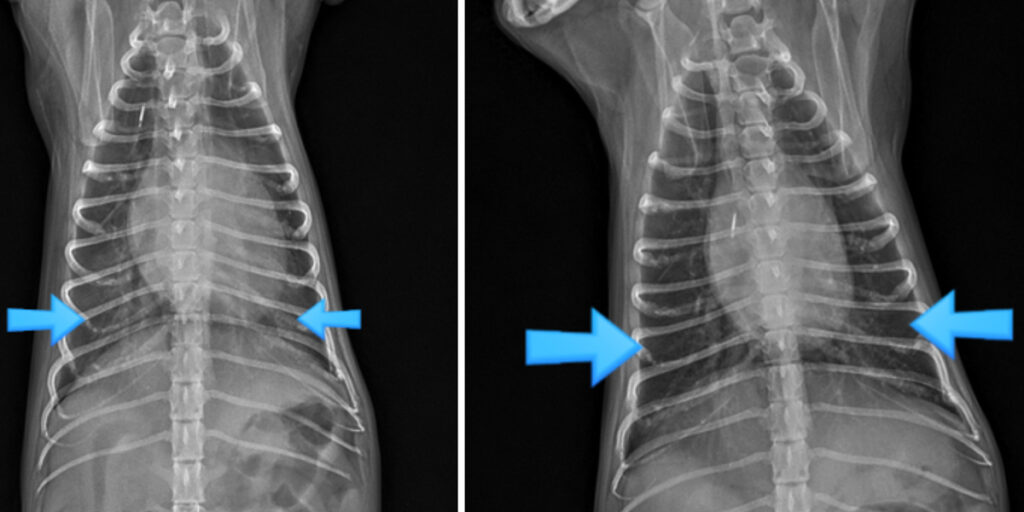

심장초음파 검사는 심장 진단의 핵심입니다

심장초음파는 엑스레이(X-ray)로는 확인할 수 없는 심장 내부 구조와 기능을 직접 확인할 수 있는 검사입니다.